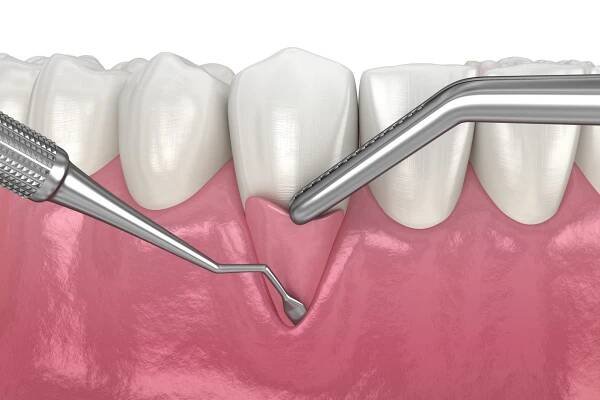

Jak často chodit na zubní hygienu, kolik vás to bude stát a komu přispěje pojišťovna